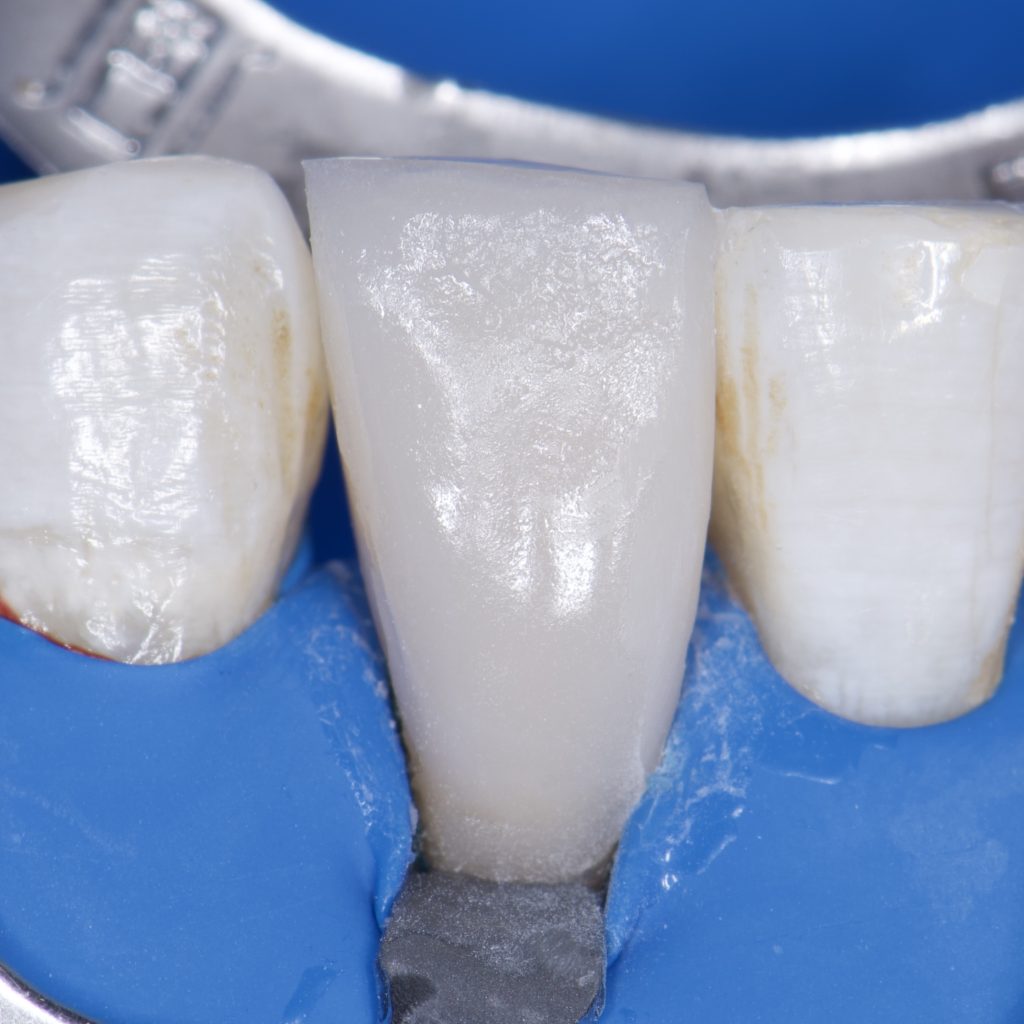

-Isolation with rubber dam

-Endodontic treatment with Bioceramic sealer and single cone

– SE clearfil bond

– Ribbond

– Direct composite restoration, layering technique